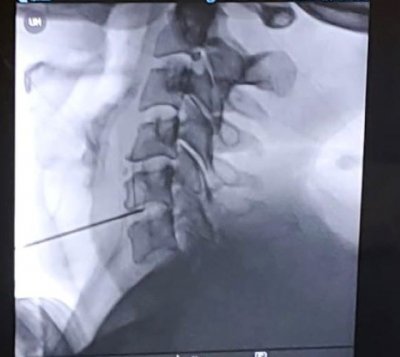

Con esta intervención no invasiva basada en la aplicación de radiofrecuencia en el disco dañado se pueden disminuir los síntomas…